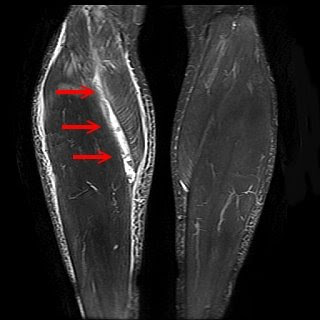

Tennis Leg / Plantaris Tendon Rupture - Radsource

Tennis Leg / Plantaris Tendon Rupture - Radsource from radsource.us

But as the tears in the tendon multiply, they cause pain from inflammation and weakening of the tendon. An achilles tendon rupture can prevent you from putting any weight at all on your leg. Treatment for quadriceps tendon tear: These tendons are the soft tissues that connect the hamstring muscle to the outer part of the knee, and they assist the hamstring muscles in bending, straightening, running, jumping, and kicking. Tennis leg / plantaris tendon rupture.